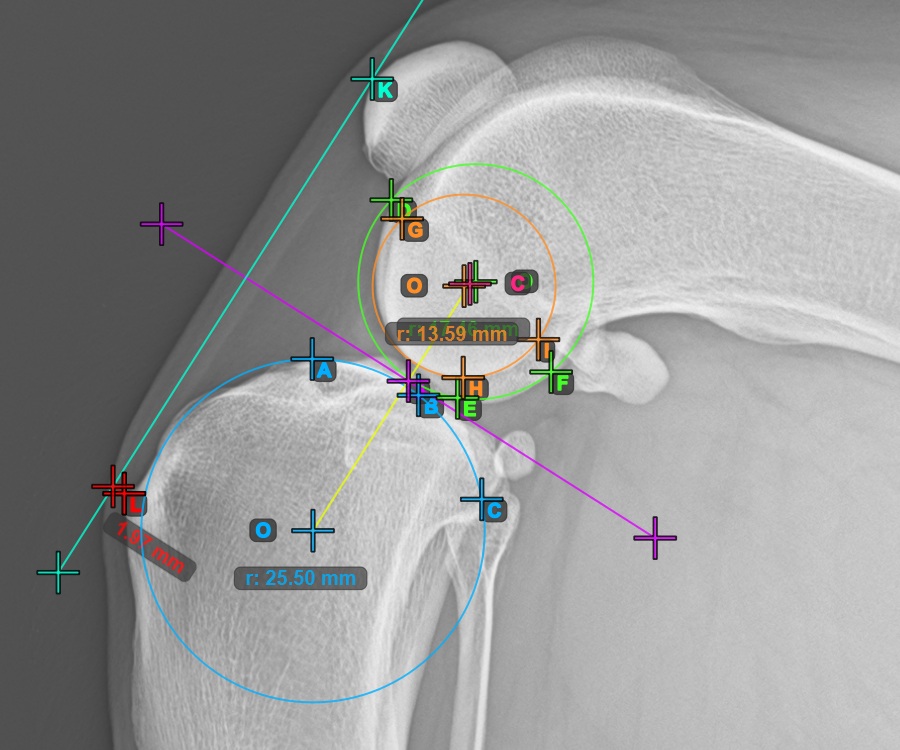

Mark one point in front of the joint on the common tangent between the two main condylus circles. A line will be drawn automatically through the marked point.

The image below represents a typical placement of the point on the common tangent between the two circles.